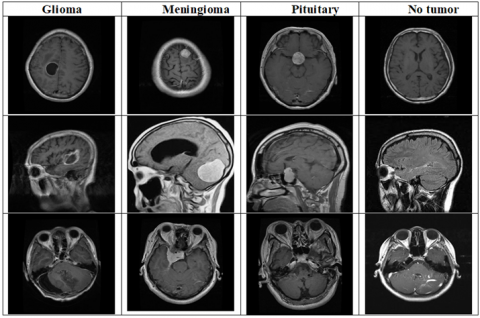

This merged dataset comprises 7023 MRI images of the human brain. For our study, we used 5712 images, classified into four categories: pituitary (1457 images), meningioma (1339 images), glioma (1321 images), and no tumor (1595 images). The no tumor images were sourced from the Br35H dataset. The image sizes vary within the dataset; therefore, the images were resized to 224×224 pixels to match the input size requirements of the three deep learning networks used.

The dataset was split into two groups: 80% allocated for training and 20% reserved for testing. Sample images collected from the database are displayed in Figure 1.

Figure 1. Sample brain MRI images from the dataset used in this study [27]